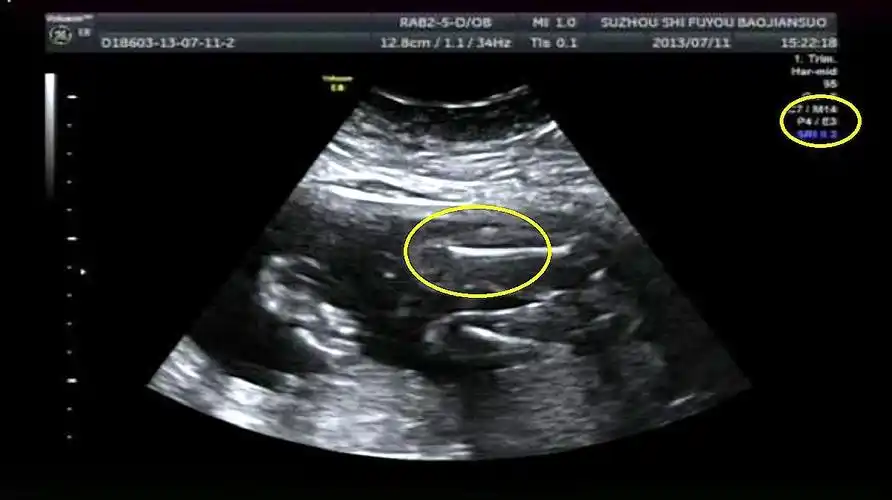

辨别胎儿性别有方法,b超单上一清二楚,再也不用求医生了!